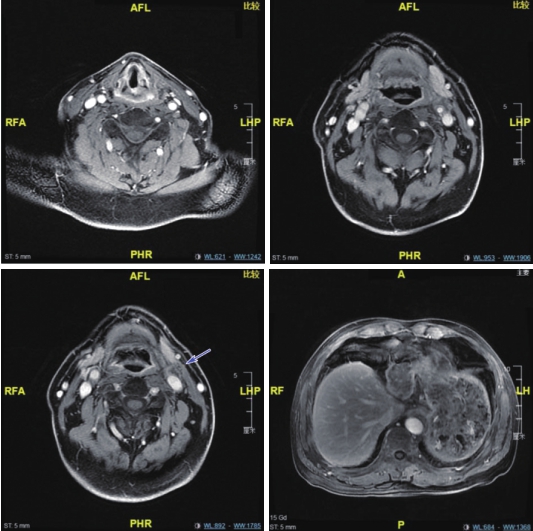

2疗程后:腹部MRI示,肝转移灶较前缩小。喉MRI示,左侧声门上型喉癌较前缩小;左颈部肿大淋巴结较前缩小。疗效评价为部分缓解(PR)(图2)。

4疗程后:腹部MRI示,肝脏术后改变,余腹部MRI未见异常。喉MRI示,左侧声门上型喉癌较前略小;左颈部肿大淋巴结部分较前缩小,囊变较前明显。疗效评价为PR(图3)。

图2 喉MRI及腹部MRI(2疗程后)

提示部分缓解

图3 喉MRI及腹部MRI(4疗程后)

提示部分缓解,肝左叶转移灶已切除